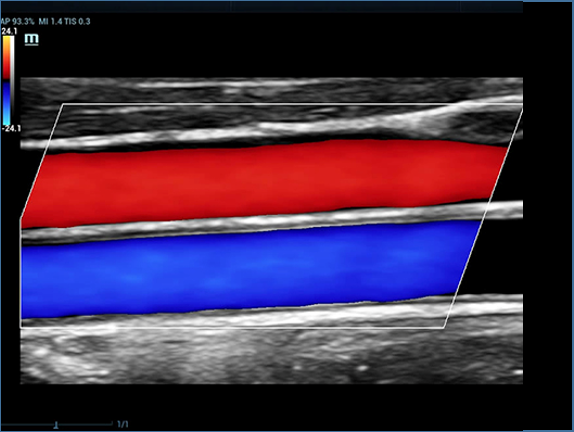

Resona 7, ĂŒstĂŒn dĂŒzeyde g?rĂŒntĂŒ kalitesine ek olarak, vaskĂŒler hemodinamik de?erlendirmesi i?in devrim niteli?indeki V Ak??? ile fetĂŒs CNS tan?lamas? i?in 3 boyutlu veri kĂŒmesinden dĂŒzlem g?rĂŒntĂŒsĂŒ alma konusunda en iyi birime sahip oldu?undan, klinik ara?t?rma yeterliklerini de art?rmaktad?r. En sezgisel, harekete dayal? ?oklu dokunmatik i?letim ile tĂŒm temel klinik ?zellikleri bir araya getiren Resona 7, ultrason yenili?i konusunda ger?ek anlamda yeni dalgalara ?ncĂŒlĂŒk ediyor.